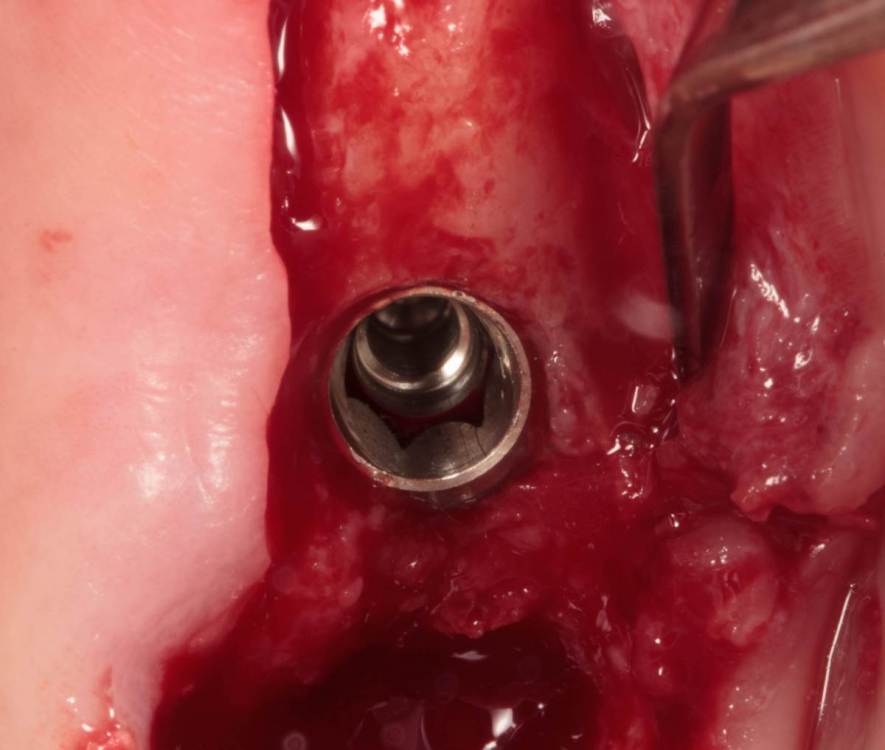

Женька Опубликовано 24 июля, 2023 Поделиться Опубликовано 24 июля, 2023 Тема ради одной фотки конечно, но всё-таки вопрос есть. Говорят МСТ профайлер не задевает стенки имплантата. Кмк, всё-таки задевает. Или всё-таки кажется? По кейсу: 2 имплантата, оба по шаблону. Черт дёрнул пройти глубже чем планировал в 1.6, фрезой перфо не создал, но кортикалку в ноль убрал. И при отслойке всё-таки порвал немного. Тампонировал губками, пробы отрицательные. Вроде нигде не перемудрил в этот раз, @АнтонТЛТ ? 3 Ссылка на комментарий

Raystom Опубликовано 24 июля, 2023 Поделиться Опубликовано 24 июля, 2023 @Женькакажется. Там юбка направляющего пина не даёт портить стенки. Ссылка на комментарий

Женька Опубликовано 24 июля, 2023 Автор Поделиться Опубликовано 24 июля, 2023 @Raystom я про эти участки Ссылка на комментарий

Raystom Опубликовано 24 июля, 2023 Поделиться Опубликовано 24 июля, 2023 @Женька хотя да, если присмотреться, то есть небольшое снятие фаски шейки по внутреннему контуру. Ссылка на комментарий

Irouil Опубликовано 25 июля, 2023 Поделиться Опубликовано 25 июля, 2023 Кстати, да, присоединяюсь к замечанию @АнтонТЛТ - зачем профайлер под заглушку?) Ссылка на комментарий

Женька Опубликовано 25 июля, 2023 Автор Поделиться Опубликовано 25 июля, 2023 @Irouil Думал формики поставить, но в последний момент передумал Ссылка на комментарий